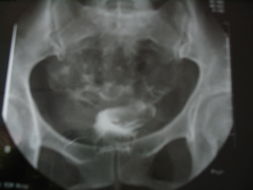

输卵管造影是不孕不育症中的常用的检查,号称不孕症金剪手。是通过导管向子宫腔及输卵管注入造影剂,用X线透视及摄片,根据造影剂在输卵管、及盆腔内的显影情况,来了解输卵管是否通畅、或阻塞部位的一种检查方法。

(该检查损伤小,痛苦小,在有经验的医生操作下能对输卵管堵塞作出正确诊断,准确率较高,是用来了解输卵管是否通畅及通畅的程度和具体堵塞部位的最常用的检查方法)